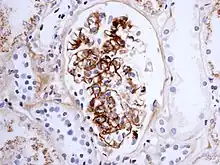

Histologically, IgA nephropathy may show mesangial widening and focal and segmental inflammation. Diffuse mesangial proliferation or crescentic glomerulonephritis may also be present. Immunofluorescence shows mesangial deposition of IgA often with C3 and properdin and smaller amounts of other immunoglobulins (IgG or IgM). Early components of the classical complement pathway (C1q or C4) are usually not seen. Electron microscopy confirms electron-dense deposits in the mesangium that may extend to the subendothelial area of adjacent capillary walls in a small subset of cases, usually those with focal proliferation.

The disease derives its name from deposits of immunoglobulin A (IgA) in a granular pattern in the mesangium (by immunofluorescence), a region of the renal glomerulus. The mesangium by light microscopy may be hypercellular and show increased deposition of extracellular matrix proteins. In terms of the renal manifestation of Henoch–Schönlein purpura, it has been found that although it shares the same histological spectrum as IgA nephropathy, a greater frequency of severe lesions such as glomerular necrosis and crescents were observed. Correspondingly, HSP nephritis has a higher frequency of glomerular staining for fibrin compared with IgAN, but with an otherwise similar immunofluorescence profile.[4]

For an adult patient with isolated hematuria, tests such as ultrasound of the kidney and cystoscopy are usually done first to pinpoint the source of the bleeding. These tests would rule out kidney stones and bladder cancer, two other common urological causes of hematuria. In children and younger adults, the history and association with respiratory infection can raise the suspicion of IgA nephropathy. A kidney biopsy is necessary to confirm the diagnosis. The biopsy specimen shows proliferation of the mesangium, with IgA deposits on immunofluorescence and electron microscopy. However, patients with isolated microscopic hematuria (i.e. without associated proteinuria and with normal kidney function) are not usually biopsied since this is associated with an excellent prognosis. A urinalysis will show red blood cells, usually as red cell urinary casts. Proteinuria, usually less than 2 grams per day, also may be present. Other renal causes of isolated hematuria include thin basement membrane disease and Alport syndrome, the latter being a hereditary disease associated with hearing impairment and eye problems.